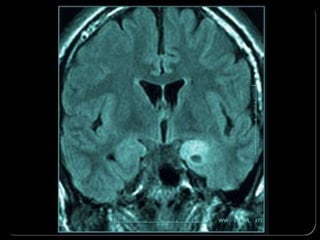

Brain scan

Detailed images of the brain from CT or MRI scans

can help doctors rule out tumors or blood clots as

a possible cause of seizures. This information is

essential in planning surgery to treat epilepsy

 CT and MRI scans reveal the structure of the brain,

which can be useful for identifying brain tumors,

cysts, and other structural abnormalities.